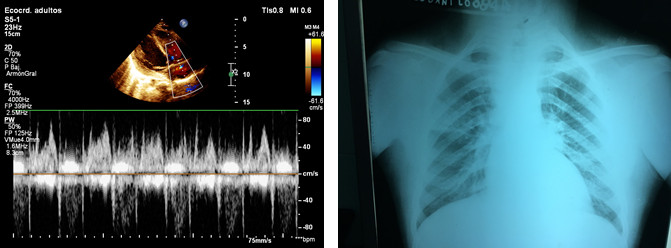

Volver a los detalles del artículo Embolismos sépticos destructivos pulmonares y sistémicos en la endocarditis infecciosa